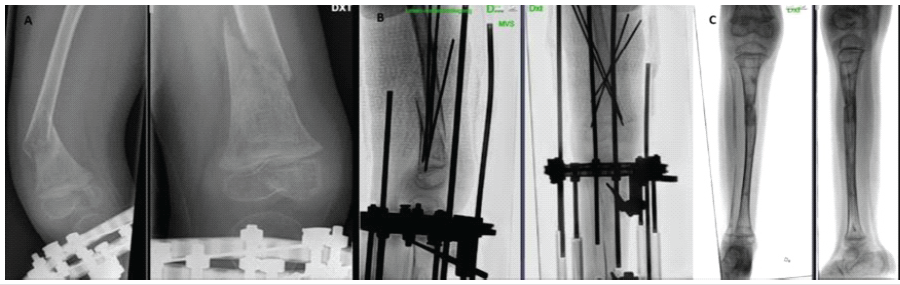

To correct the LLD, the patient underwent lengthening surgery of the short lower limb on the unaffected side with a circular external fixator. A low-energy proximal tibial osteotomy was performed, and an ostectomy of the fibula was made, and at the same time, both the proximal fibula and the distal fibula were fixated to the tibia with transosseous wires (Fig. 2). No surgery was performed on the femur, and the external fixator did not include the femur. Three weeks after surgery, the patient had a non-traumatic femoral fracture on the operated side (Fig. 3a). Given the absence of significant trauma and the presence of NF1 and MEK inhibitor therapy, the fracture was considered pathological. Management included plaster casting and K-wire fixation (Fig. 3b). Four weeks after fixation, plaster and K-wires were removed (Fig. 3c and d). Lengthening process resulted in a 4 cm gain, equivalent to 17% of the original tibial length (4/24 cm). Approximately 2 months after hardware removal, a refracture of the femur occurred at the same site (Fig. 4a), which was again treated with K-wire fixation and plaster (Fig. 4b).

Figure 4: (a) Refracture at the right distal femur 2 months after plaster and K-wire removal (b) Fracture fixation with K-wires and plaster (c) Valgus deformity of the right lower limb.

Four weeks later, the external fixator and K-wires were removed, and a long-leg cast was applied. During the subsequent 5 weeks of immobilization, the patient developed a progressive valgus deformity of the operated lower limb (Fig. 4c) and a proximal migration of the distal fibula suggesting instability at the distal tibiofibular joint. To address this, bone transport of the distal fibula (Fig. 5a) was performed. To maintain alignment, a distal positioning screw was inserted. However, the patient experienced recurrence of proximal fibular migration due to screw cut-out and fixation failure (Fig. 5b,c). Throughout the course of treatment, the contralateral limb with the PN remained skeletally unaffected.